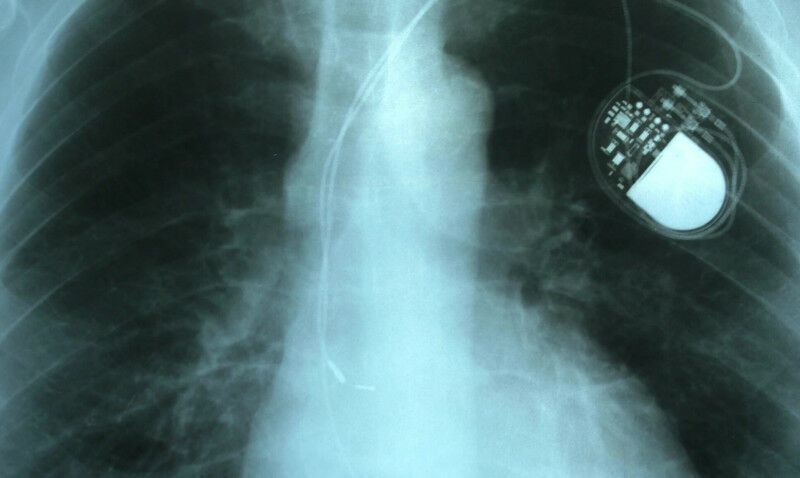

Academics from Imperial and NTU Singapore are developing better ways to protect implantable active devices, such as pacemakers.

Academics from Imperial and NTU Singapore are developing better ways to protect implantable active devices, such as pacemakers. Imperial has opened its first overseas research and innovation centre in Singapore to strengthen collaboration between the UK and Singapore. Imperial Global: Singapore will see Imperial's scientists working closely with university, industry, government, and third-sector partners in Singapore. The first research programme taking place at the new centre is a major S$20million grant in collaboration with Nanyang Technological University, Singapore (NTU Singapore) to improve the security of medical devices and health data. The programme, IN-CYPHER , will leverage Imperial's expertise in this area to establish Singapore as a global leader in health cybersecurity and AI for healthcare as it bolsters research and funding in these emerging areas. "Imperial Global: Singapore will connect with world-leading science and technology in Singapore and Southeast Asia and open a gateway for stronger collaboration with the UK." Hugh Brady President of Imperial College London The centre, which builds on the longstanding Imperial-NTU Singapore strategic partnership , will enable scientists to rapidly scale new scientific breakthroughs and technology to societal benefit and commercialisation in Southeast Asia. Imperial staff and PhD students will be working in cutting-edge laboratories at the centre alongside partners from Singapore's top universities and institutes.